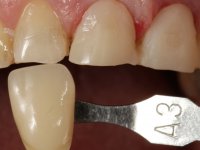

It was important to involve the patient in assessing the aesthetic advantage of increasing the height of central superior incisors. For this purpose, a direct mock-up was molded in-mouth, with non-adhesive composite resin. Once the patient agreed to the course of treatment, a silicon matrix was prepared, for subsequent production of provisional veneers. After installing a gingival deflection cord, dental preparation was performed, with special consideration to the fact that the insertion of both veneers would be frontal. Accordingly, mesial and distal walls did not require convergence. The incisal edge was prepared perpendicular to the axis of insertion. After preparation, IDS (immediate dentin sealing) was carried out. A “one-step, double mix technique” was adopted for impression, using putty soft and light silicon. Provisional veneers were produced using dual polymerization composite resin. Color selection was done in the same session.